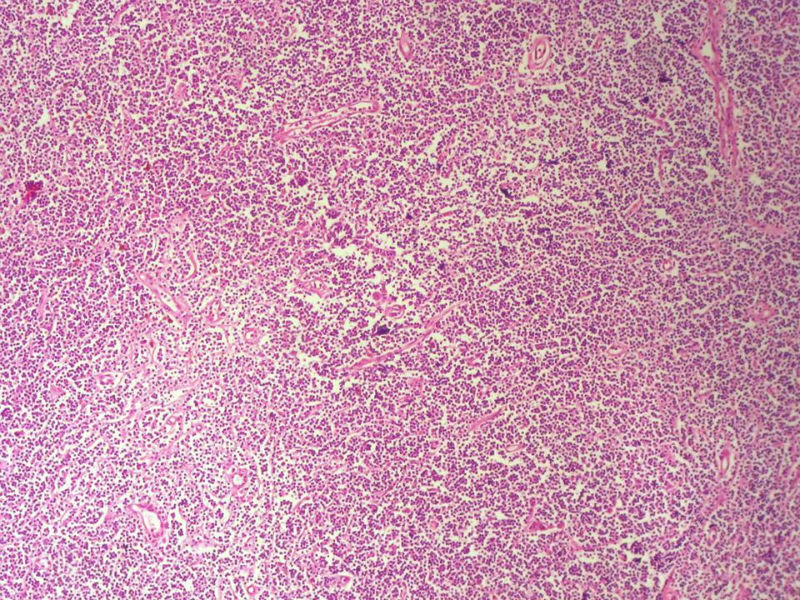

男,49岁,左眼睑球结膜下肿物2个月,手术切除。检查肿块3X2X2厘米,切面灰红色,质软。

淋巴样细胞。细胞形态单一,细胞小。主要鉴别:

1)粘膜相关淋巴组织淋巴瘤

2)小细胞性淋巴瘤/慢性淋巴细胞性白血病

3)套细胞淋巴瘤

形态结构与细胞大小,似不支持滤泡性淋巴瘤。

淋巴瘤  细胞小  形态单一  主要考虑小B细胞淋巴瘤